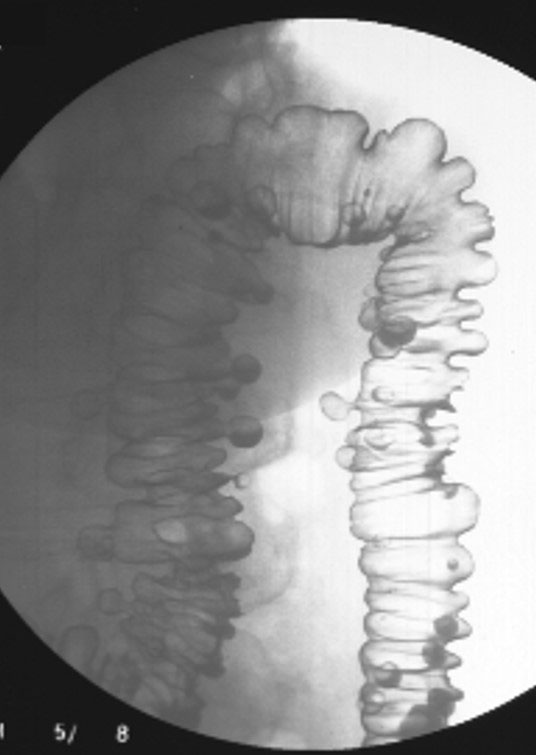

Do diverticula usually occur singly or in groups?

In groups, not singly.

Where do diverticula most commonly occur?

The sigmoid colon.

Why is the sigmoid colon the most common site for diverticula?

It is narrow and experiences high pressure during stool movement toward the rectum.